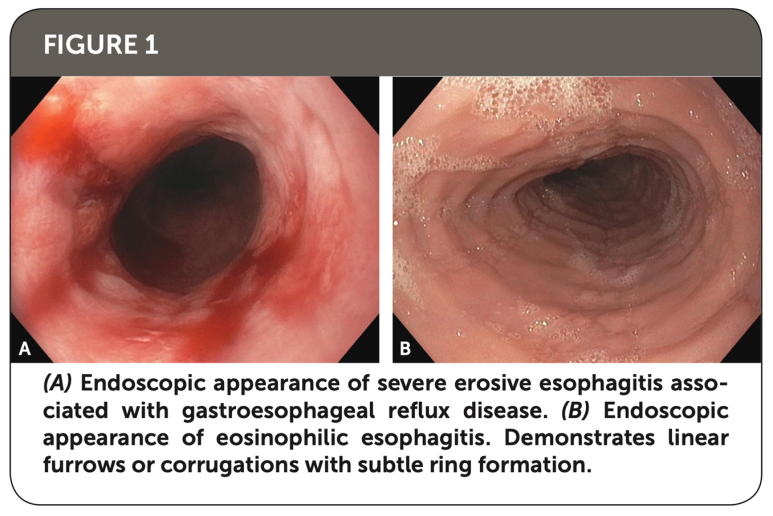

미란성 식도염의 경우 붉은 발적과 발적병변 주변에 부종 소견이 있는 반면 호산구 식도염의 경우 Furrow와 ring이 특징적인 소견입니다.